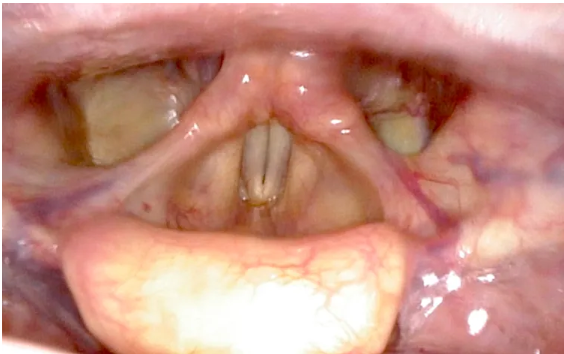

Adequate transoral exposure is a critical prerequisite for successful transoral surgery, particularly when targeting deep or distal structures such as the supraglottic larynx or hypopharynx. Achieving a clear, stable surgical corridor requires the use of specialized retractors.

TORS offers a minimally invasive approach for the resection of selected tumors in the supraglottic larynx and hypopharynx. Using the robotic system’s enhanced 3D visualization, tremor-free motion, and articulated instruments, surgeons can perform precise resections with en bloc removal with adequate oncologic margins. Benefits of the minimally invasive approach include reduced morbidity, shorter hospital stays, improved swallowing outcomes, and the potential to avoid tracheostomy or more extensive open procedures.